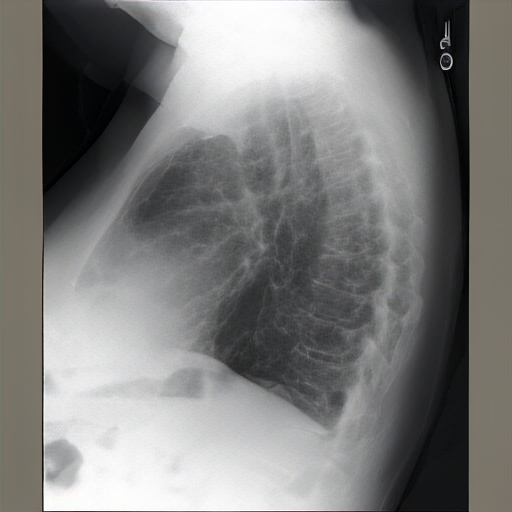

As compared to the previous radiograph, there is pneumonia in the right upper lobe, better visible on the lateral radiograph and moderately dense on the frontal radiograph, appearing more extensive. A newly appeared retrocardiac lung opacity suggests possible re-expansion by a malignancy. A pre-existing lung opacity in the left retrocardiac region has increased substantially. The opacity is likely large, potentially pneumonia in the lateral location. The opacity is confirmed on both the lateral and frontal radiographs, consistent with the clinical presentation.

Frontal and lateral views of the chest are obtained. Relative subtle posterior left base linear opacity, best seen on the lateral view, appears similar to scarring. Aside from minimal linear atelectasis/scarring, no scarring is noted. No focal consolidation. No pleural effusion or pneumothorax. The cardiac silhouette is stable. Left humeral costochondral calcifications are noted. No definite pulmonary edema is seen.